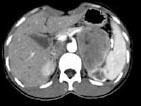

问题 女,36岁,无任何症状,体检时超声发现左侧肾上腺区占位,CT扫描如图所示,应诊断为 ( )

选项 A、左肾上腺髓样脂肪瘤 B、左肾上腺转移瘤 C、左肾上腺囊肿 D、左肾上腺嗜铬细胞瘤 E、左肾上腺腺瘤

答案 E